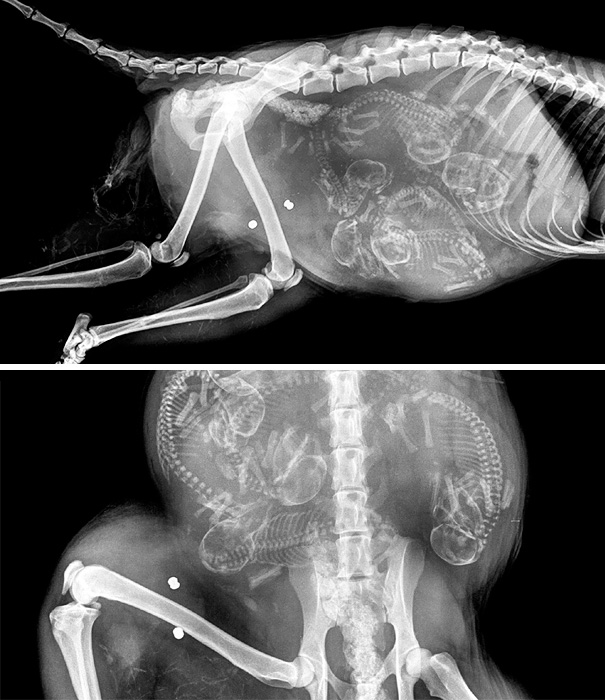

Unikāli rentgena attēli ar dzīvniekiem gaidībās

Bieži negadās publiski redzēt dzīvnieku rentgena uzņēmumus. Turklāt šie rentgena uzņēmumi ir veikti dzīvniekiem, kuri ir mazuļu gaidībās. Tagad ikvienam ir iespēja ielūkoties, kā dzīvnieku mazuļi attīstās savu mammu vēderos.